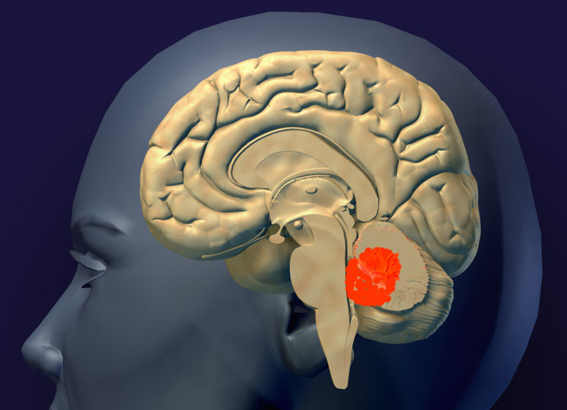

髄芽腫のできる場所

赤く塗ってあるのが髄芽腫の最も多い場所です。小脳虫部から発生して第4脳室を埋めるように大きくなります。前の方にある脳幹部を圧迫しますが,多くの場合は脳幹部に浸潤(入り込むこと)しません。発生部位は,小脳虫部が8割くらい,小脳半球が2割くらいです。小脳,脳幹部,脳室の説明はここをクリックすると詳しく出ます。

- 乳児から幼い子供たち(中央値5歳)の小脳にできます

- 髄液の出口(第4脳室)をふさぐために頭の中に水がたまってしまいます

- 発生部位は,小児例の7割が小脳虫部に発生しするが,成人になるにつれ小脳半球に発生することが多くなる